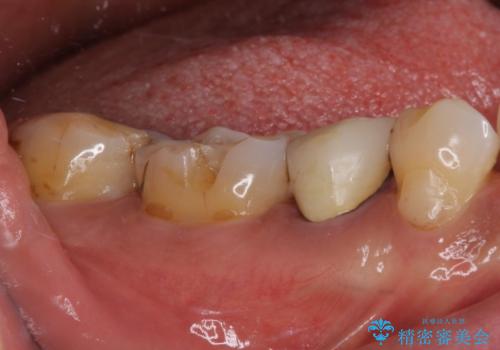

- セラミックが剥がれたり、歯質が欠けたりした奥歯を気にして来院された患者様です。

咬合力が強い方であったため、2歯をフルジルコニアクラウンにて補綴することとしました。